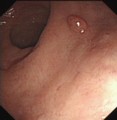

十二指肠球部溃疡

腺瘤

锯齿状腺瘤

管状腺管腺瘤

绒毛状腺瘤

肠息肉

增生性息肉